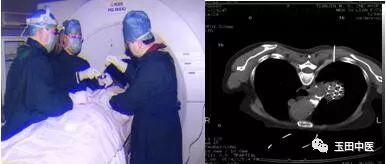

我院肿瘤中心拥有玉田县第一台放射性碘125粒子治疗计划系统,具备开展肿瘤微创介入放疗技术的条件。粒子计划系统精准和高效的核心特点使其可以胜任多种放疗技术,适用于不同疾病的治疗需求,极大地提高肿瘤放射治疗的速度和准确性。

②现开展了肿瘤病人近距离放疗---- CT引导下放射性粒子植入